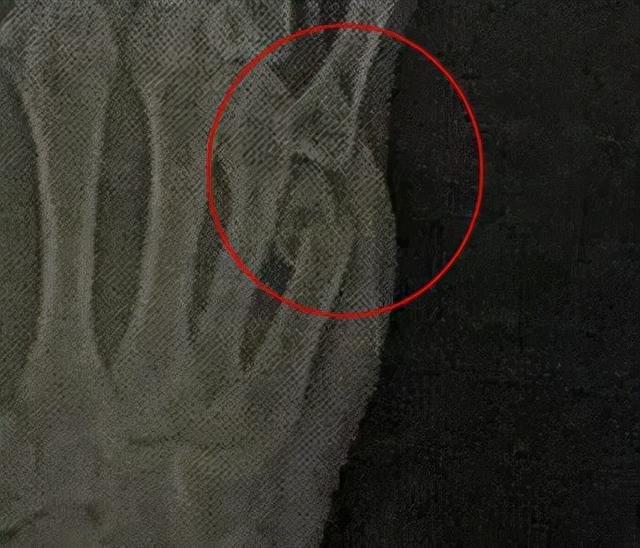

等医院的拍片结果出来后,曾庆瑞这才得知自己的右手第5掌骨已经骨折。“只要嫌犯落网,这点伤不算什么…”知道诊断结果后,曾庆瑞虽然有些吃惊,但仍旧无怨无悔。